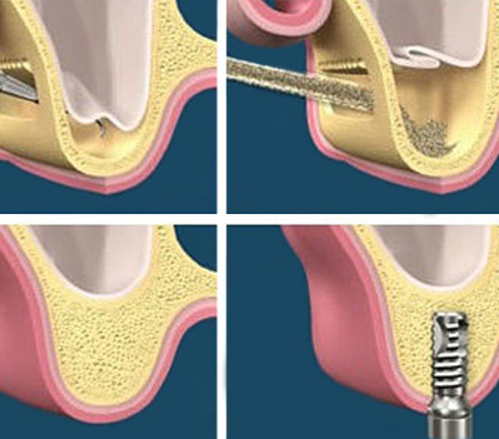

Sinus Lift Surgery

In order to successfully place dental implants you need sufficient bone. In certain situations dentist need to perform specific procedures in order to create bone volume. One such procedure is sinus lift. The maxillary sinuses are empty rooms that have nothing at all in them. When upper teeth are removed, there is often just a thin wall of bone separating the maxillary sinus and the mouth. Dental implants need bone to hold them in place so when the sinus wall is very thin, it is impossible to place dental implants in this bone. There is a solution called a sinus graft or sinus lift graft. The dental implant surgeon enters the sinus and sinus membrane is then lifted upward and donor bone is inserted into the floor of the sinus. After several months of healing, the bone becomes part of the patient’s jaw and dental implants can be inserted and stabilised in this new sinus bone. The sinus graft makes it possible for many patients to have dental implants when years ago there was no other option other than wearing loose denture.